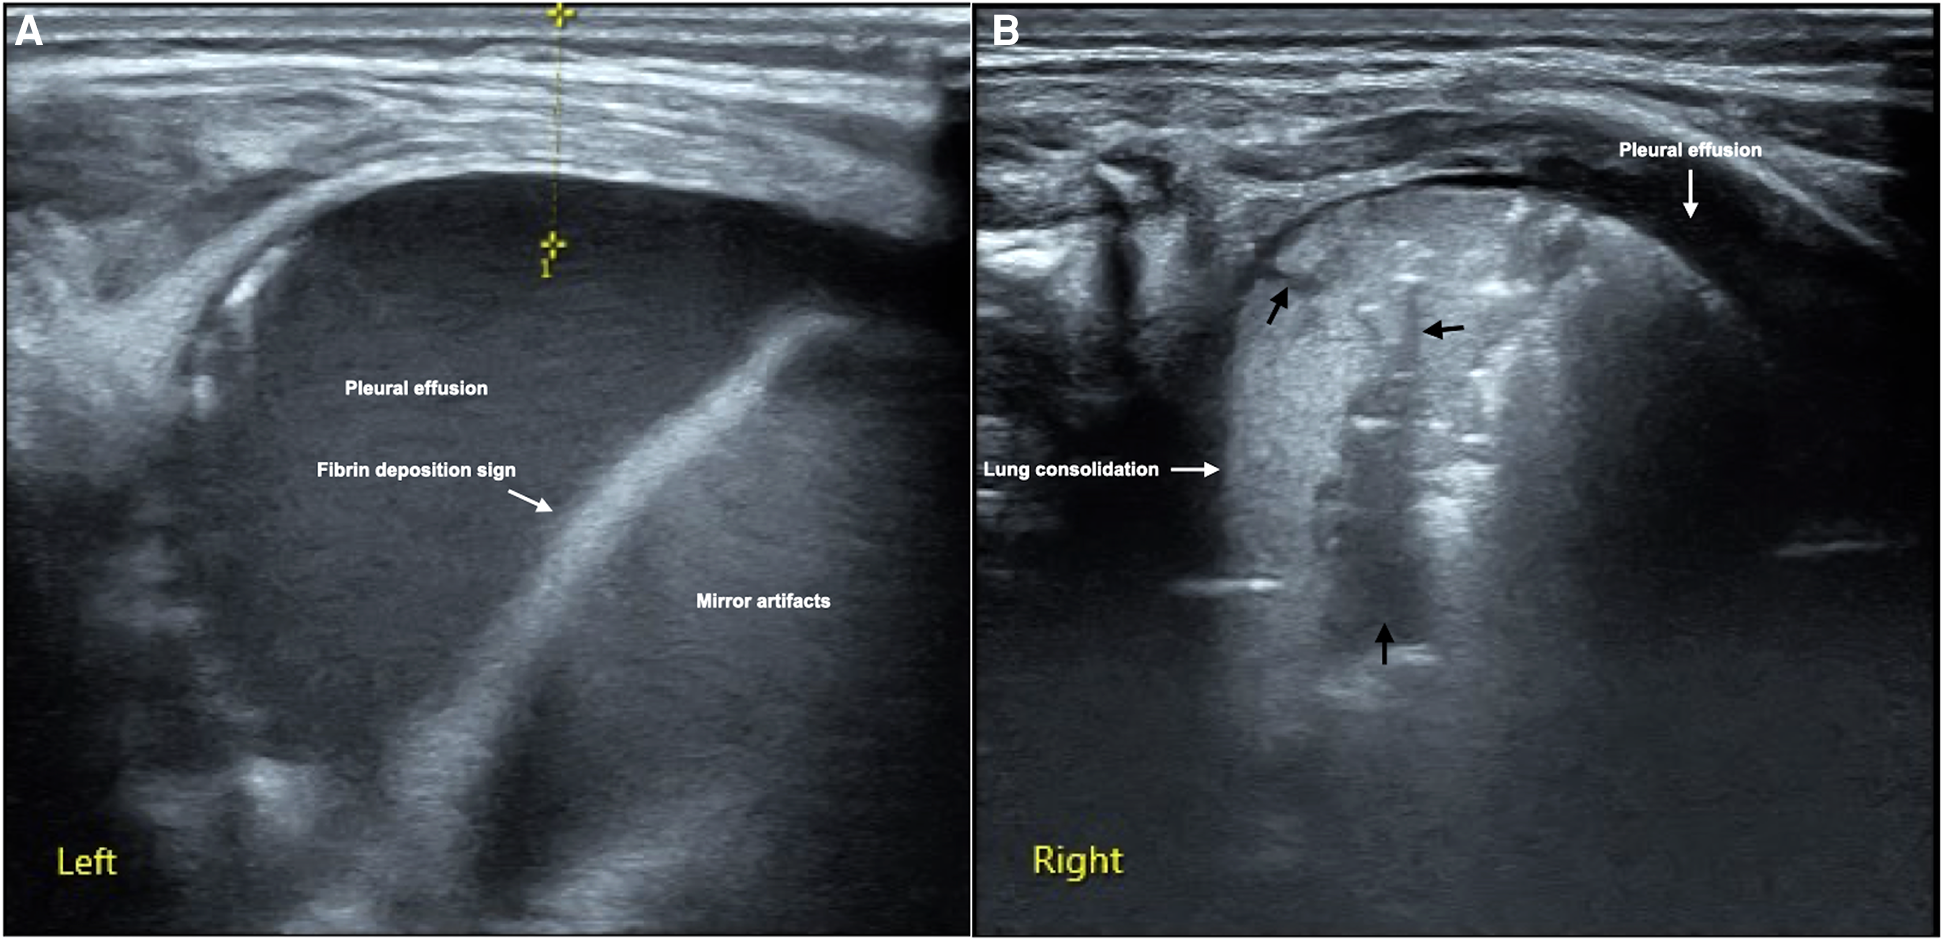

It can be see from Table 2, the major and common LUS manifestations are lung consolidation (92.9%), air bronchograms (92.9%), fluid bronchograms (81%), pleural effusion (85.7%), shred signs (83.3%), B-lines (100%) and pleural line abnormalities (100%). The fibrin deposition sign is a rare ultrasonic sign of PH, which was found among 12 patients (28.6%) (Figure 1). Sometimes, dynamic fluid bronchograms (DFB) could be observed in severe PH patients under real-time ultrasound (Supplementary Video S1). While in normal lungs, only a few infants can have a small number of B-lines, but with no lung consolidation and pleural effusion (Figure 2).

Figure 1

LUS manifestations of neonatal PH. This is a male term infant delivered by cesarean section at gestational age 40+3 weeks with birth weight of 3,890 g. He was admitted to NICU at 10 min of birth due to fetal distress, severe birth asphyxia and dyspnea after resuscitation. Physical examination found that the infant's respiratory rate increased by more than 70/min with significant retraction, palpable wet rales on auscultation. LUS showed massive pleural effusion and mirror artifacts, and fibrin deposition sign in the left thoracic cavity (A), while the right lung should significant lung consolidation accompanied with fluid bronchograms (thick black arrows), and a small amount of pleural effusion (B). 30 ml of hemorrhagic effusion was extracted from the left thoracic cavity by pleural puncture.

4.4.2. Fibrin deposition sign

It has been confirmed that pleural effusion in infants with PH was confirmed as bloody fluid by pleural puncture (12) (Figure 1). In the pleural effusion of a few patients with severe PH, the fiber strip-like shadow and its artifacts formed by the destruction of blood cells and fibrin deposition could be seen, which was called the fibrin deposition sign (10) (Figure 1). The fibrin deposition sign can be seen moving with the fluctuation of the fluid under real-time ultrasound (Supplementary Video S2). Although this sign is uncommon, it is only seen in PH patients while not in other kinds of lung diseases (such as MAS and pneumonia) and normal lungs in the present study, therefore, this sign has specific value for the diagnosis of PH. As we can seen from Table 4, although the sensitivity of this sign in the diagnosis of PH is only 28.6%, the specificity is as high as 100% with the PPV was also 100%.